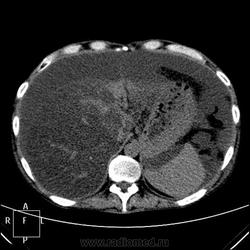

. Не станете же Вы утверждать, что бери-бери или гиповитаминоз В1 присущи исключительно мужчинам? Согласна исключить из вероятностей патогенеза этого пациента Синдром Мейгса:).  . Здесь печень замещена жировой тканью, гепатоциты отсутствуют на 90-95%. Разовьём тему функции печени?

. Здесь печень замещена жировой тканью, гепатоциты отсутствуют на 90-95%. Разовьём тему функции печени?

Ух и "здоровая" же у вас печень!

Тут воды полно, саму печень надо поискать, я постаралась поиграть окнами, чтоб её было видно. Не особо и увеличена. Уже.

Печень по цвету (плотности) должна быть почти такой же, как и селезенка (50-70 единиц), а в данном случае 10 единиц, вода в брюшной полости 5-7 единиц. Так что нормальных гепатоцитов там кот наплакал.

А в брюшной полости - я не специалист по КТ, но киста в поджелудочной железе какая то странная и что за объизвествления? Нет ли там рака?

Интерстициальный отек легких. Хронический калькулезный панкреатит. Киста хвоста поджелудочной железы, без биопсии уверенно раковое перерождение не исключить. Киста сальниковой сумки /вероятно тоже панкреатического генеза/. Жировой гепатоз печени с портальным циррозом /биопсия/. Камень устья? пузырного протока. Геморрагические кисты почек??? Асцит.

Камень в месте слияния пузырного и общего печеночного протоков. Думаю, что корковые и медуллярные кисты почек, да, но может ли быть в них кровоизлияние, вызванное ДВС-синдромом, например, или они изначально были геморрагическими - не знаю. Четкие контуры у кисточек, формой на микроинфаркты не тянут.